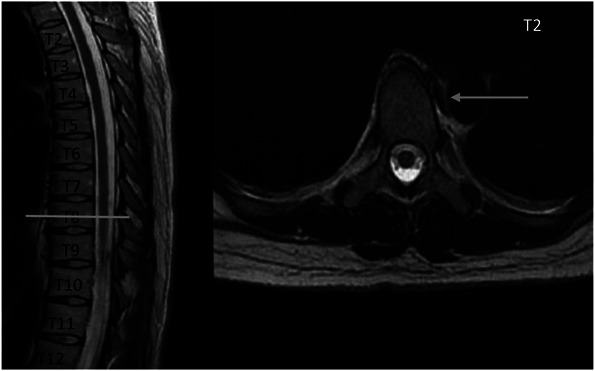

Clinical presentation: An adult patient who consulted about a 1 year and a half of flank pain refractory to analgesic management and hypoesthesia on palpation in the left T8 dermatome, therefore, pain of radicular origin was suspected. MRI of the thoracic spine was requested, showing an image suggestive of vascular malformation at the level of T8. After identification of the lesion, the patient was taken to spinal angiography to delimit the vascular malformation, finding an image suggestive of spinal venous vascular ectasia associated with a low-flow fistula of paravertebral location at T8. Subsequently, the case was discussed by a multidisciplinary team that established endovascular embolization as the best option for treatment. Thus, achieving complete occlusion of the lesion without complications and a slow improvement of the symptoms.